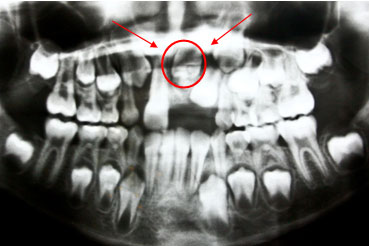

*This panoramic x–ray shows an impacted central incisor which is dilacerated or has a bent root that needs to be surgically and orthodontically pulled out.